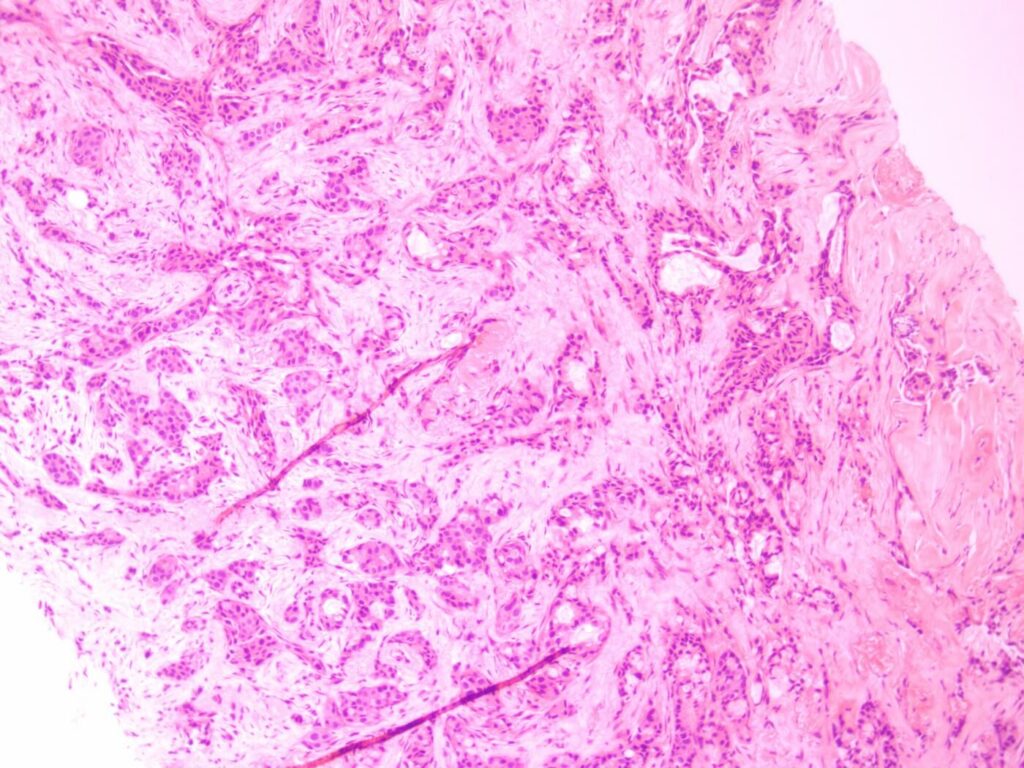

After the specimen is received in the histology lab, gross (macroscopic) examination is performed. The specimen is properly oriented, examined and appropriate representative section(s) taken, including surgical margins where appropriate.

The representative sections (or some small specimens in entirety) are then put in small cassettes and put through a series of processing steps. Ultra-thin slices of the tissue are then cut and put on glass slides. The tissue is stained and is then examined by pathologists to give a diagnosis.